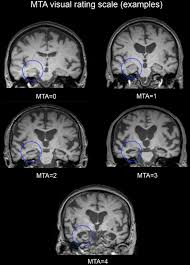

Neuroimaging In Dementia An Update For The General Clinician Progress In Neurology And Psychiatryprogress In Neurology And Psychiatry

Neuroimaging In Dementia An Update For The General Clinician Progress In Neurology And Psychiatryprogress In Neurology And Psychiatry from wileymicrositebuilder.com

Lewy, the scientist who discovered them. Loss of substantia nigra hyperintensity on 7 tesla mri of parkinson's disease, multiple system atrophy, and progressive supranuclear palsy. Besides nuclear imaging methods, the clinical utility of structural neuroimaging with magnetic resonance imaging (mri) for differential comparison between dementia with lewy bodies and alzheimer's disease. You also might see things that aren't there, called hallucinations. Lbd is a term that covers two conditions that have similar. Protein deposits, called lewy bodies, develop in nerve cells in the brain regions involved in thinking, memory and movement (motor control). Certain nuclear scans of the brain, including positron emission. How is lewy body dementia (ldb) diagnosed? Dr michael firbank discusses his study using functional mri in lewy body dementia and alzheimer's disease at the newcastle university institute. Focal atrophy in dementia with lewy bodies on mri: Memory loss is not always an early symptom. Lewy body dementia (lbd) is a type of progressive dementia. Many people also experience changes in alertness including daytime sleepiness, confusion or staring spells.

Protein deposits, called lewy bodies, develop in nerve cells in the brain regions involved in thinking, memory and movement (motor control). It's rare in people under 65. Also, there is a helpline for support provided by dementia. Dementia with lewy bodies (dlb), also known as lewy body disease, is a neurodegenerative disease (a synucleinopathy to be specific) related to parkinson disease. Dementia with lewy bodies appears to be the second most common form of dementia, accounting for about one in five cases. Further research is needed to clarify the relationships among them. Some scans (ct and mri scans) look at how the different parts of the brain fit together, rather than how the parts work together. The deposits are called lewy bodies and are named after friedrich h. Dementia is the name for problems with mental abilities caused by gradual changes and damage in the brain. Lewy body dementia, also known as dementia with lewy bodies, is the second most common type of progressive dementia after alzheimer's disease dementia. Certain nuclear scans of the brain, including positron emission. This may include a magnetic resonance imaging (mri) or computed tomography (ct) scan of the brain. After alzheimer disease (ad), dementia with lewy bodies (dlb) is one of the most common types of degenerative dementia.